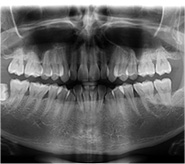

初診檢查拍片費用

口內牙病篩查費用

正畸方案拔牙費